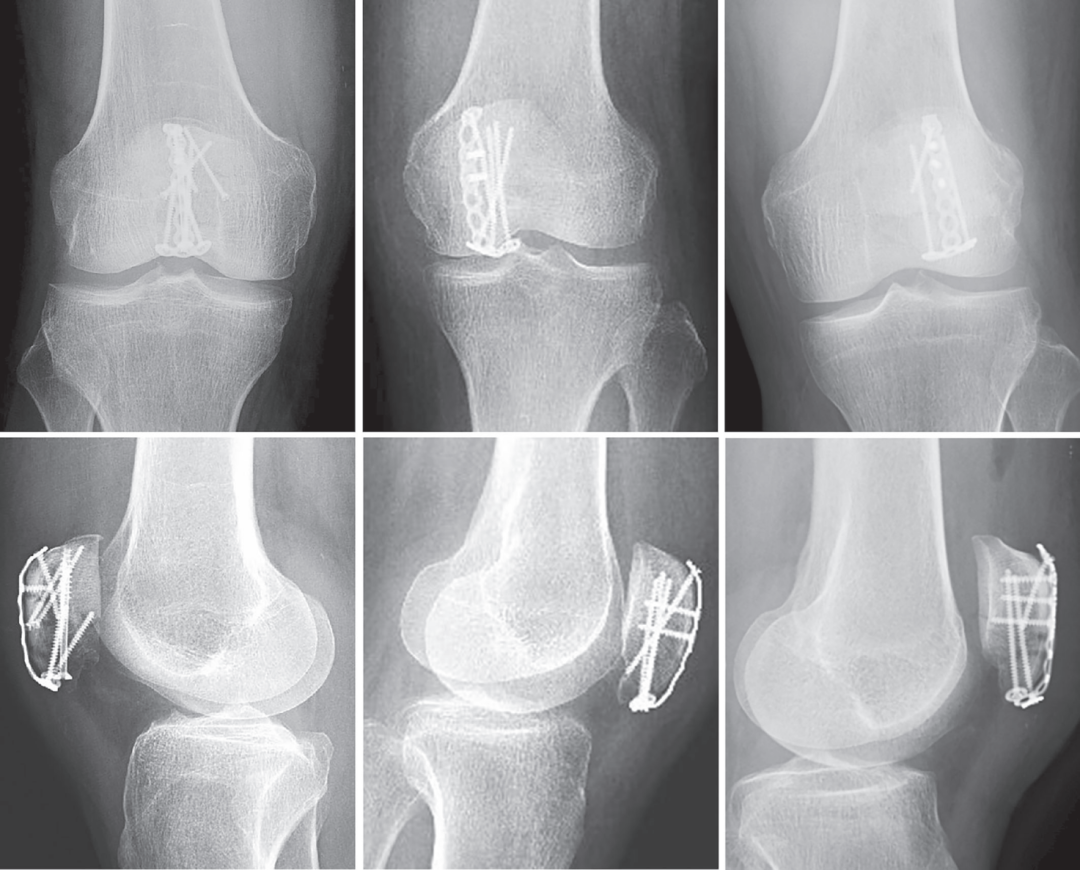

图1. 患者术前影像学检查示髌骨下极多发骨折,AO分型为C1.3;

(A) x线片正、侧位片;(C)髌骨三维重建;(D)矢状面断层图像显示远端碎片的细节。

图4. HPS术后2天x线片。(A)患者AO分型为C1.3,空心螺钉加拉力螺钉固定的正、侧位像;(C)患者5的正位和(D)侧位图像,AO分型为C1.3,没有补充螺钉固定;(E)患者25的正位和(F)侧位图像,AO分型为A1,没有补充螺钉固定。